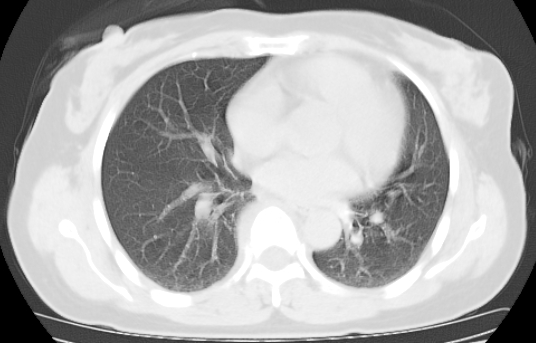

标题: CT25227:背部疼痛伴双侧胸壁痛2月,食欲差。 [打印本页]

标题: CT25227:背部疼痛伴双侧胸壁痛2月,食欲差。

肺结核并胸椎结核?请各位高手指教。

用椎体的条件来扫胸椎呀!考虑1左侧胸膜小结节形成2椎体结核并冷脓肿形成

左肺结核灶,胸椎结核并冷脓肿。

左肺结核灶,胸椎结核并冷脓肿